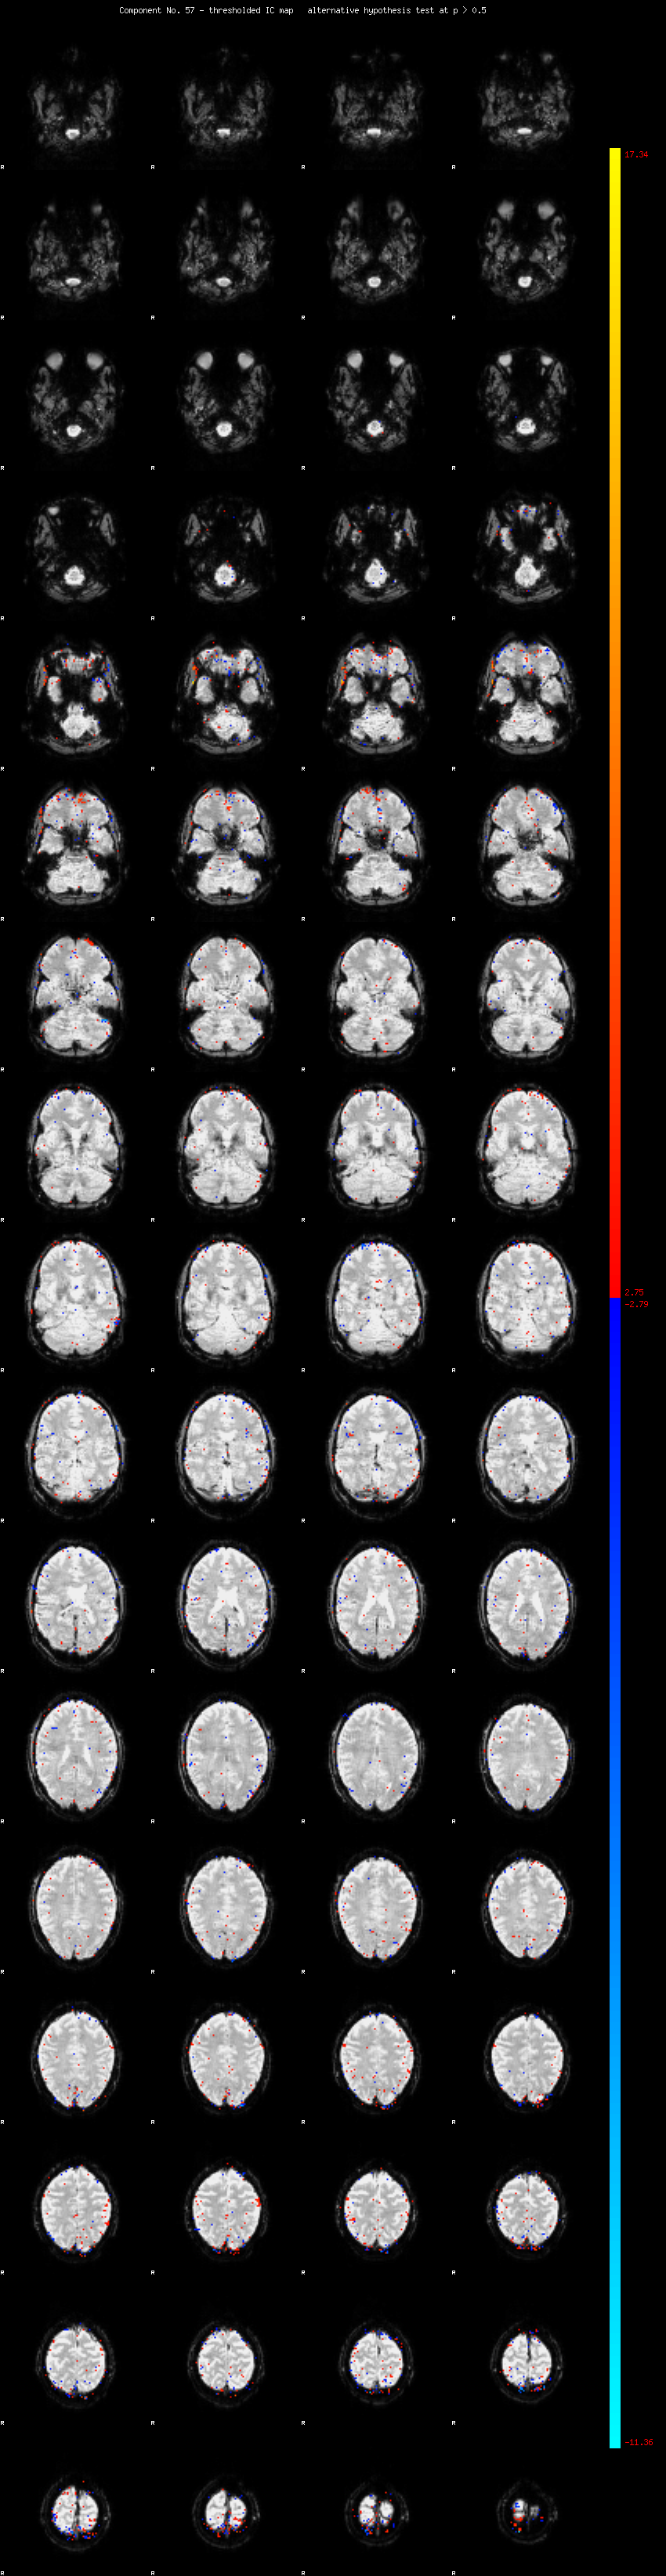

MELODIC Component 57

0.88 % of explained variance;     0.58 % of total variance